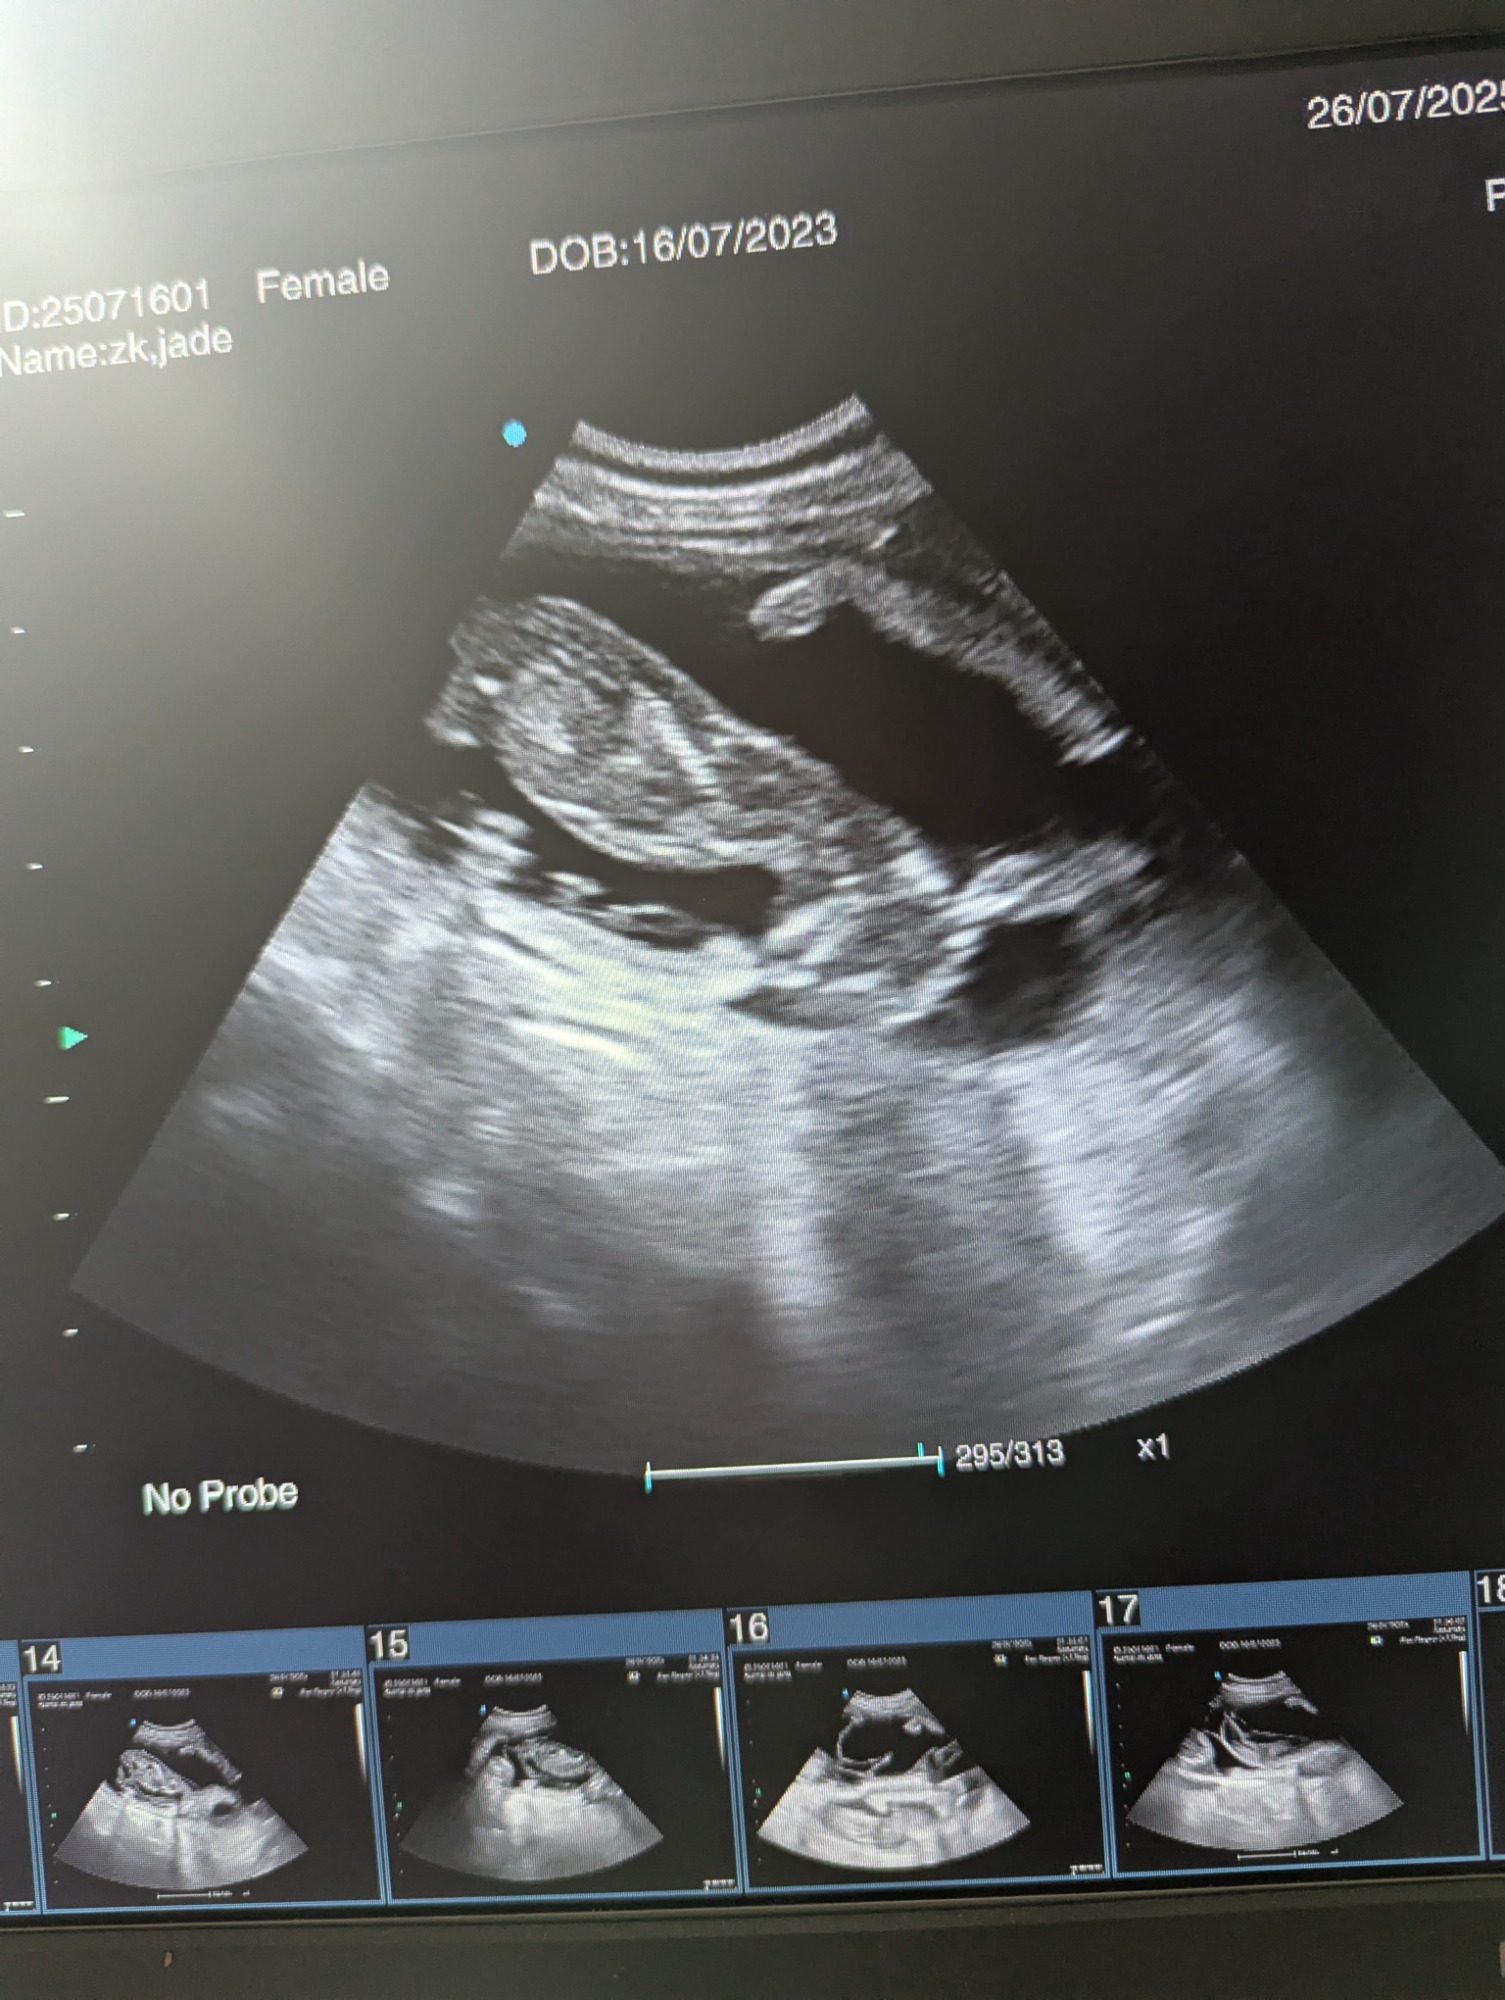

Ultrasound pregnancy scanning is a safe, non-invasive way to confirm pregnancy in dogs and cats, offering breeders and pet owners peace of mind and vital information to support responsible care. It allows us to detect gestational sacs, assess foetal development, and estimate litter size—all while ensuring the wellbeing of the animal.

Pregnancy can sometimes be detected as early as Day 18 post-mating, but scanning at this stage is not routinely recommended. Embryos are still developing and may not be clearly visible, and there is a natural risk of embryo resorption, which can lead to misleading or inconclusive results.

For the most accurate and reliable scan, we advise booking between Day 25 and Day 32, when pregnancy is more easily confirmed and foetal structures are clearer. If an early scan is performed and no pregnancy is detected, we offer a FREE complimentary re-scan after 7 days at the clinic to ensure clarity and support informed decision-making.